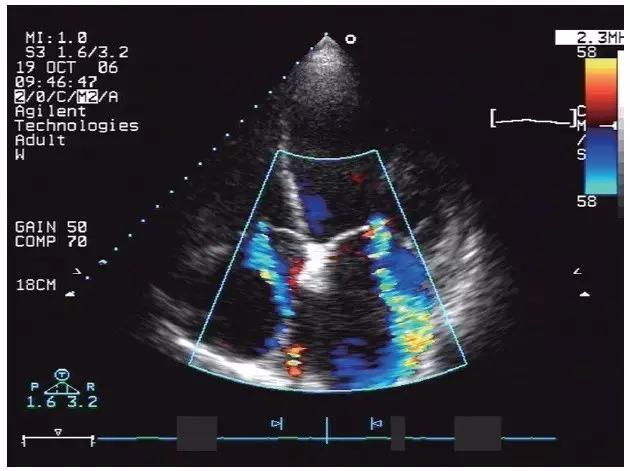

由于心肌收缩及舒张功能受损,心房和心室内的血流速度缓慢,导致彩色血流显色暗淡。由于心腔扩大,二、三尖瓣环相对扩大,造成相对性关闭不全,瓣口存在收缩期反流(图11-1-5)。

图11-1-5 扩张型心肌病二尖瓣和三尖瓣返流